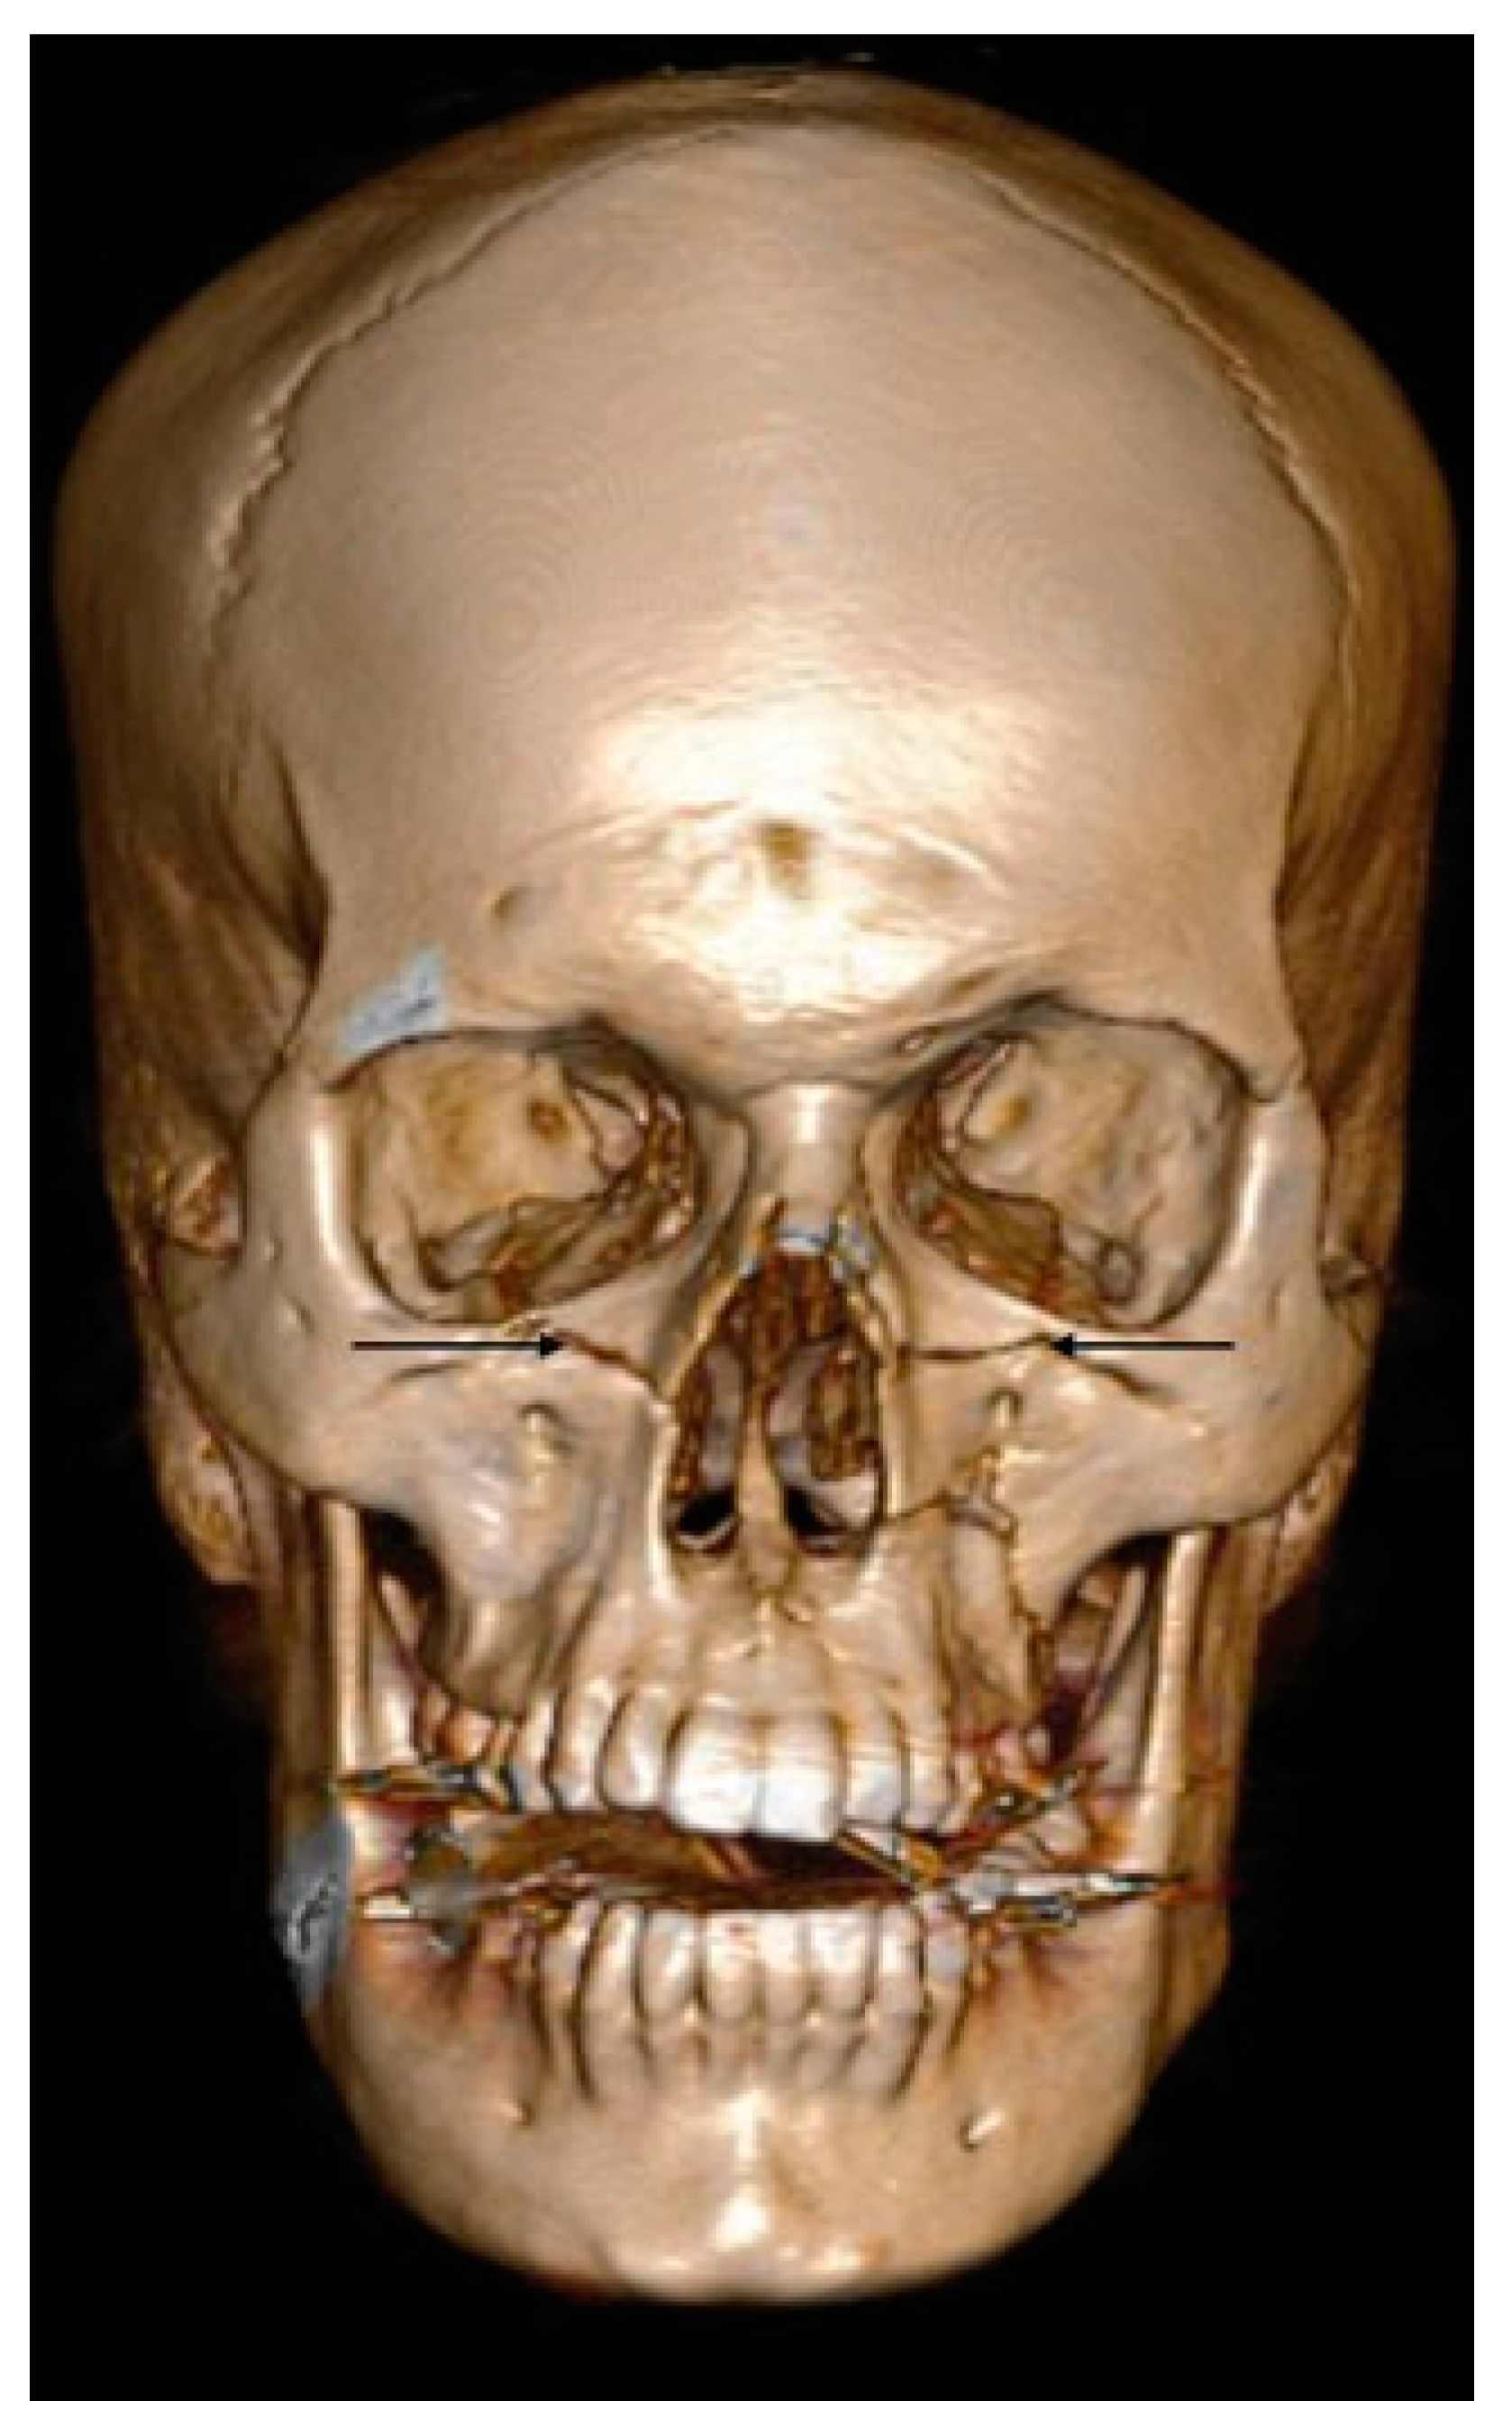

- Additional line extending from the pyriform aperture to the infraorbital rim of the same side (60%).

- D1: Additional Line Extending from the Pyriform Aperture to the Infraorbital Rim of the Same Side (34.5%)